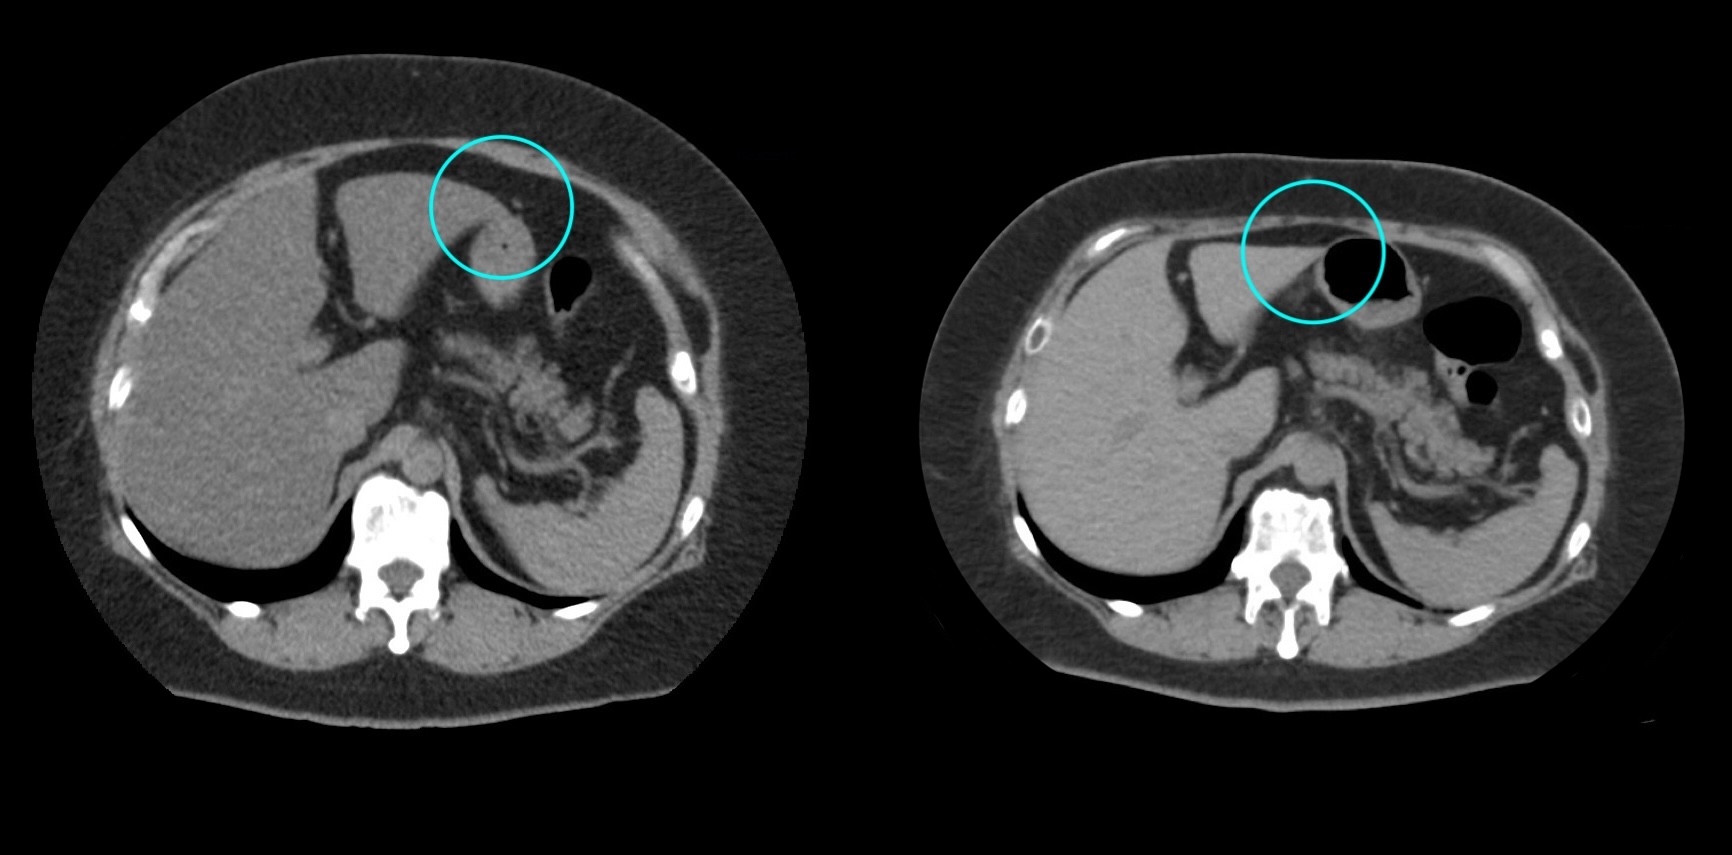

2:脂肪肝の改善

沈着した脂肪の減少による肝臓の平均CT値の増加(20から50へ)(脾臓の平均CT値は両者とも50)

bluntness of the liver edgeの改善(青色部分)